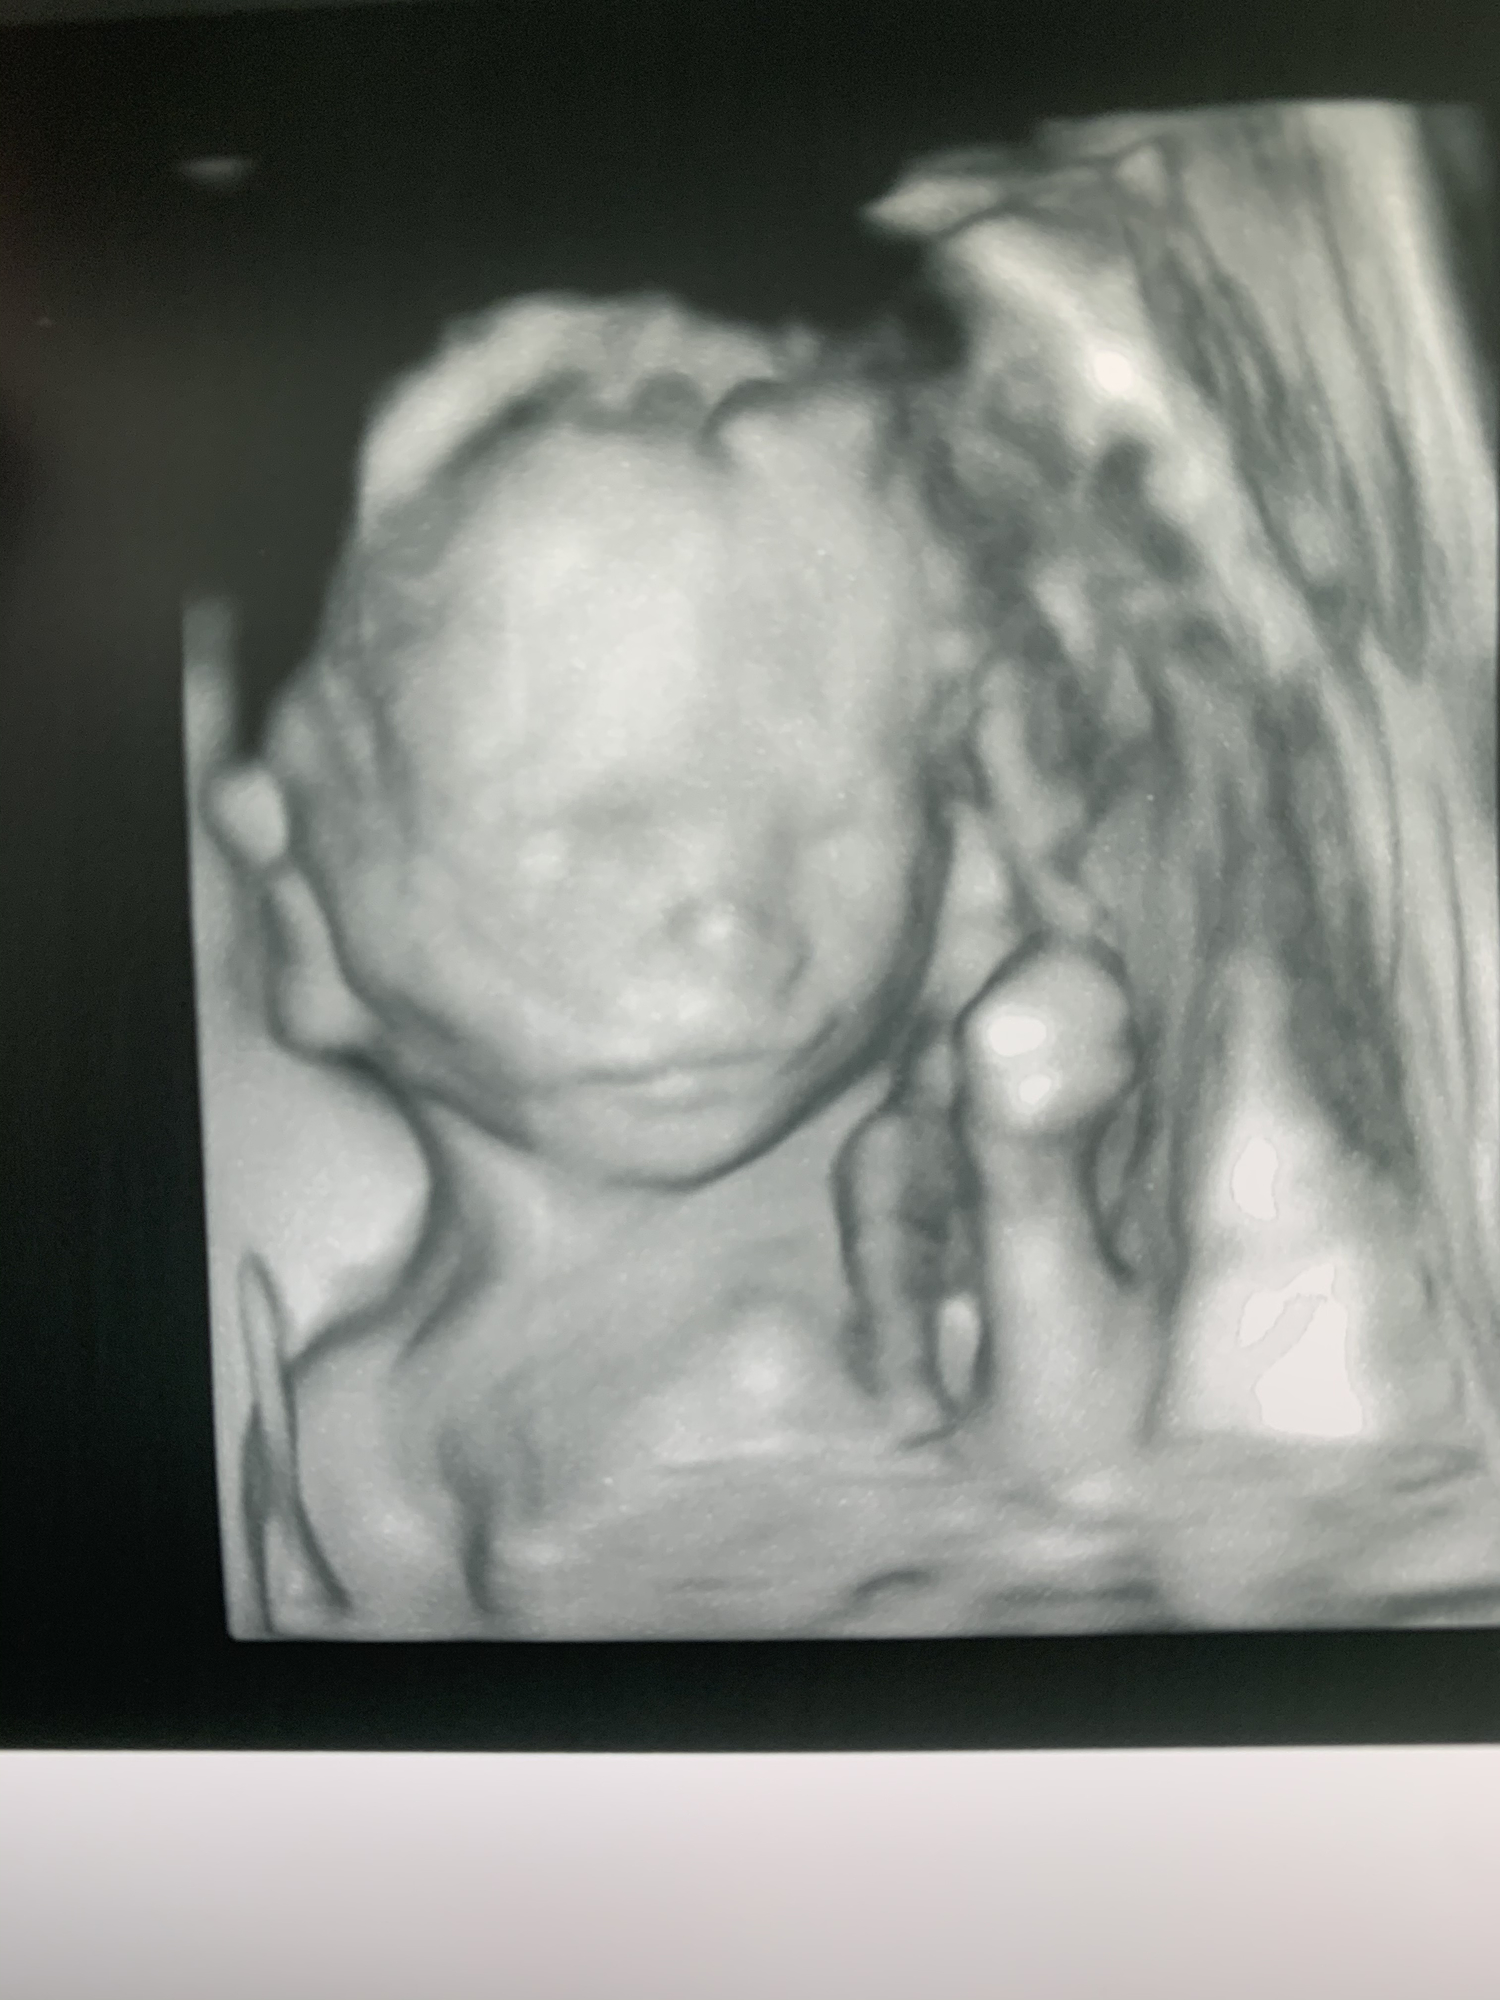

I had my anatomy scan. He is measuring big in the 78th %tile and absolutely perfect. He was moving so much she struggled to get some measurements. She got some incredible 3D pictures of him. Look at that sweet face! 😍

AS today and baby looked great and healthy! We stayed Team Green for the 4th time. The tech said she could definitely tell if it was a boy or girl, but I stayed firm and told her we for sure didn’t want to know! This was the very first time I’ve had a 3D ultrasound- Baby has similar features to his/her big sisters! Can’t wait to hold this cutie in 20 weeks 🥰